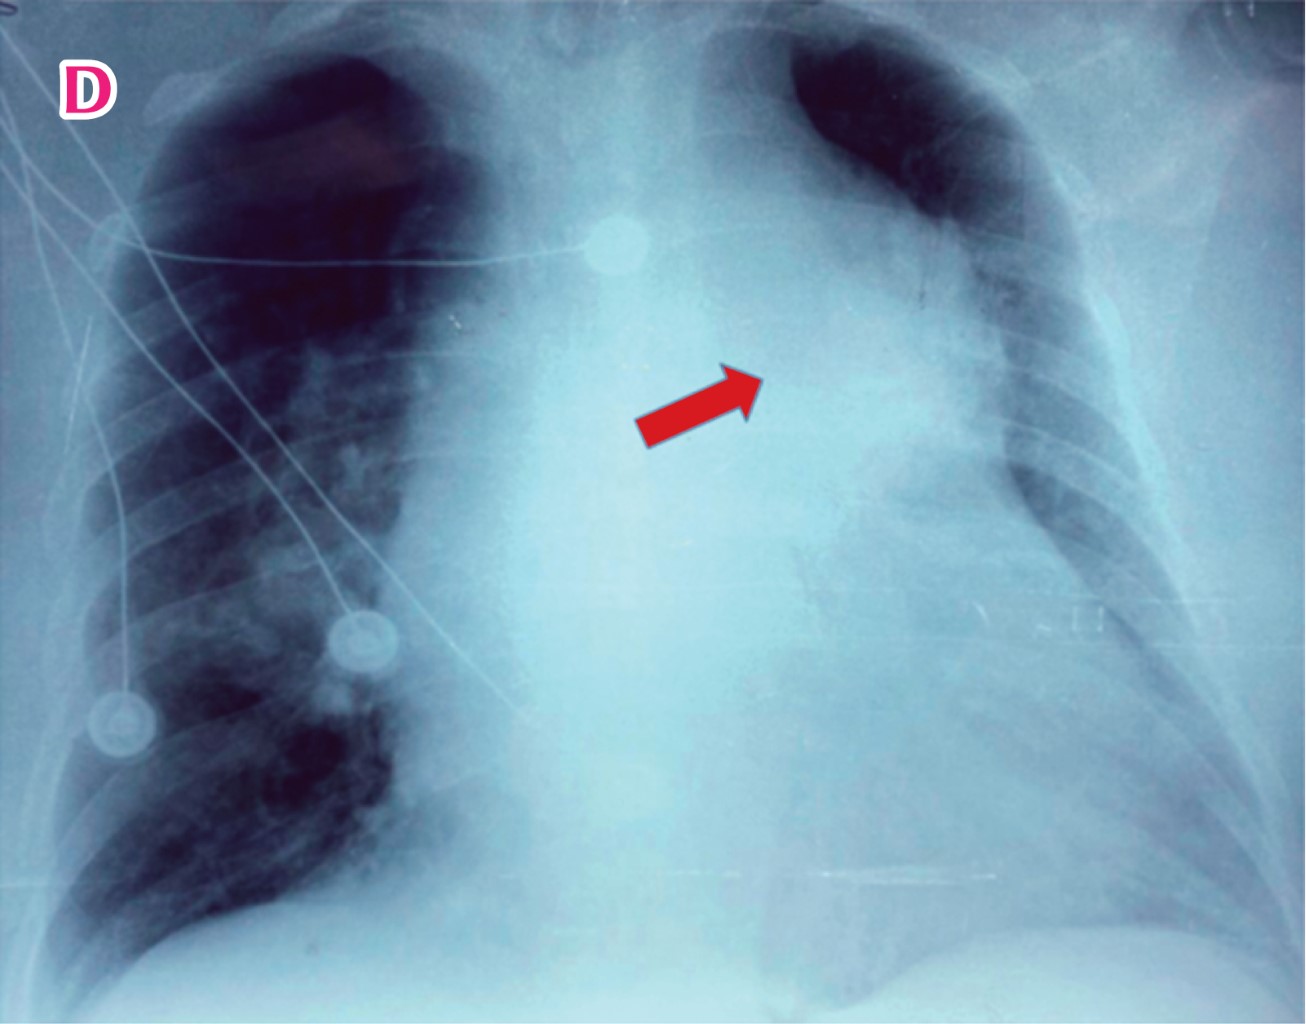

Objetivo: Describir la presentación de una disección de arteria pulmonar a la Unidad de Urgencias, la secuencia de eventos y revisión de la literatura. Reporte de caso: Paciente femenino de 59 años con cardiopatía chagásica conocida, quien acudió a urgencias por un episodio de dolor torácico repentino punzante y disnea progresiva, que evolucionó rápidamente a choque cardiogénico. Una radiografía de tórax informó un ensanchamiento severo del mediastino y cardiomegalia; por tanto, se realizó una angiotomografía torácica para descartar síndrome aórtico agudo, en la que se diagnosticó un aneurisma disecante de arteria pulmonar. El ecocardiograma transtorácico mostró un colgajo de la íntima a nivel de la arteria pulmonar y una dilatación severa. La paciente falleció en menos de 4 horas desde su llegada a urgencias sin poder acceder a tratamiento quirúrgico debido a la rápida evolución. Conclusión: La disección de la arteria pulmonar es una enfermedad rara, con una alta tasa de mortalidad. El manejo óptimo requiere un diagnóstico rápido con múltiples técnicas de imagen. Falta información sobre este tema.

Figura 3